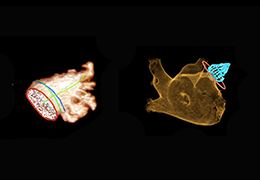

View X-Ray CT & MRI Scans Fast and Easily

Designed for surgeons, Pro Surgical 3D makes it easy to view patient scans quickly. Pro Surgical 3D facilitates the optimal 3D treatment and assessment workflows based on X-ray CT and MRI scans – and best of all, it’s FREE!

Performs 3D reconstruction and volume rendering.

Multi-planar slicing.

Oblique slicing.

Instant and interactive surface extraction and export to STL and PLY formats.